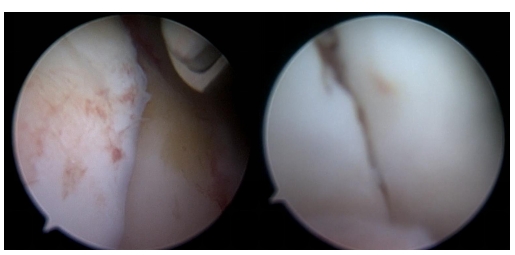

术中关节镜下显示关节面骨折线复位前后对比,可见关节外复位后,关节面基本平整,达到解剖复位。

术中,谷文光团队紧密配合,首先修复损伤的半月板,镜下清楚地看到了股骨髁部的骨折线,用复位钳在关节外复位,镜下监视骨折线移位及复位情况,复位满意后克氏针临时固定。随后按照术前方案,由后向前在股骨髁内打入导针,并沿导针置入空心拉力螺钉。由于采用微创手术治疗,术后患者刀口渗出及感染几率明显减低,住院时间由此也显著缩短,术后4-5天刀口清洁换药两次后出院继续康复治疗。